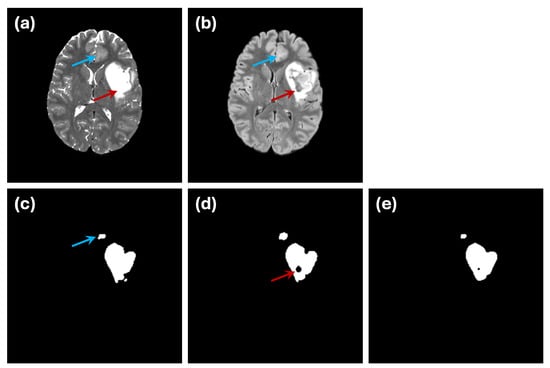

3.1. Image Dataset

5.2. Accuracy of Golden Truth Labels

5.3. Limitations